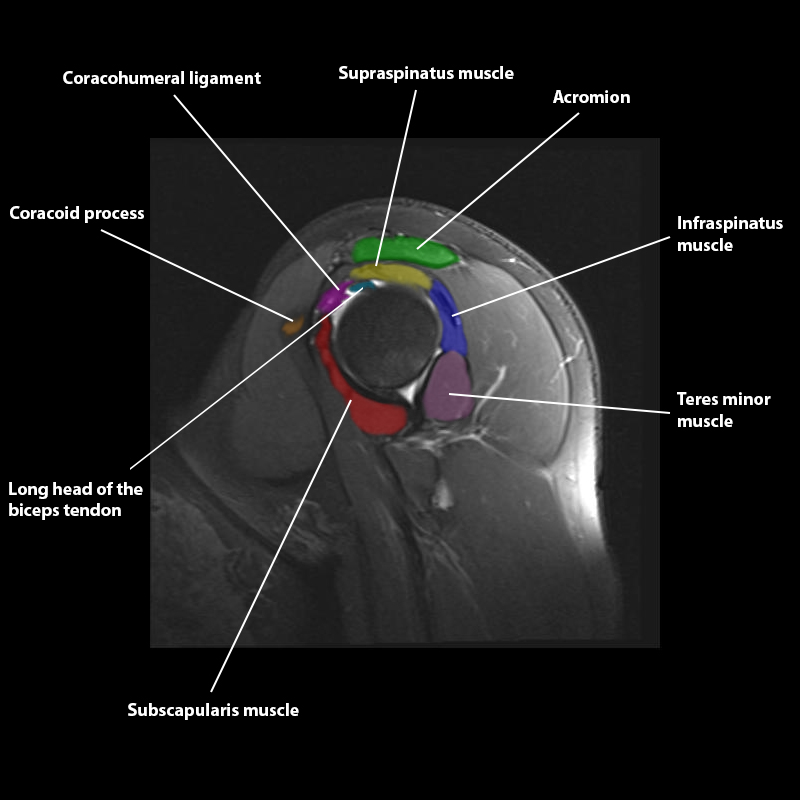

Shoulder MRI Anatomy